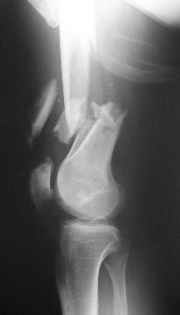

Perfect for retrograde nail + lag screw with this large a distal fragment and this much meta-diaphyseal comminution and this degree of soft tissue injury.

after treatment of open fracture